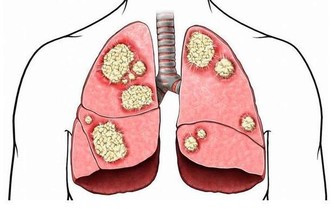

3 肺部排毒

每天早晨到室外空氣新鮮的場所做深呼吸運動,同時深吸氣時緩抬雙肩,然後呼氣時放鬆雙肩,進行3-5次深呼吸後,應作有意識地咳嗽幾下,使肺部、氣管中的廢物和毒素隨咳嗽氣流而排出體外